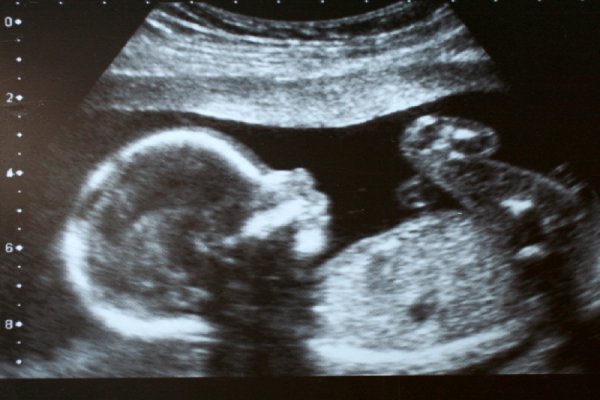

Anomaly Scan (Level 2 / TIFFA)

Detailed fetal structural scan between 18 to 22 weeks. Essential to detect any congenital abnormalities.

Growth Scan

Used in the third trimester to check the baby's size, amniotic fluid levels, and placenta health. A key scan for safe delivery planning.